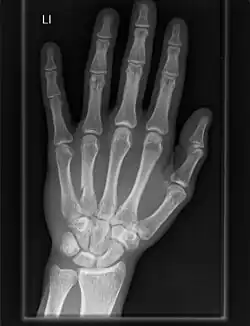

The carpometacarpal (CMC) joints are five joints in the wrist that articulate the distal row of carpal bones and the proximal bases of the five metacarpal bones.

- The second metacarpal articulates primarily with the trapezoid and secondarily with the trapezium and capitate.

- The third metacarpal articulates primarily with the capitate,

- The fourth metacarpal articulates with the capitate and hamate.

- The fifth metacarpal articulates with the hamate.